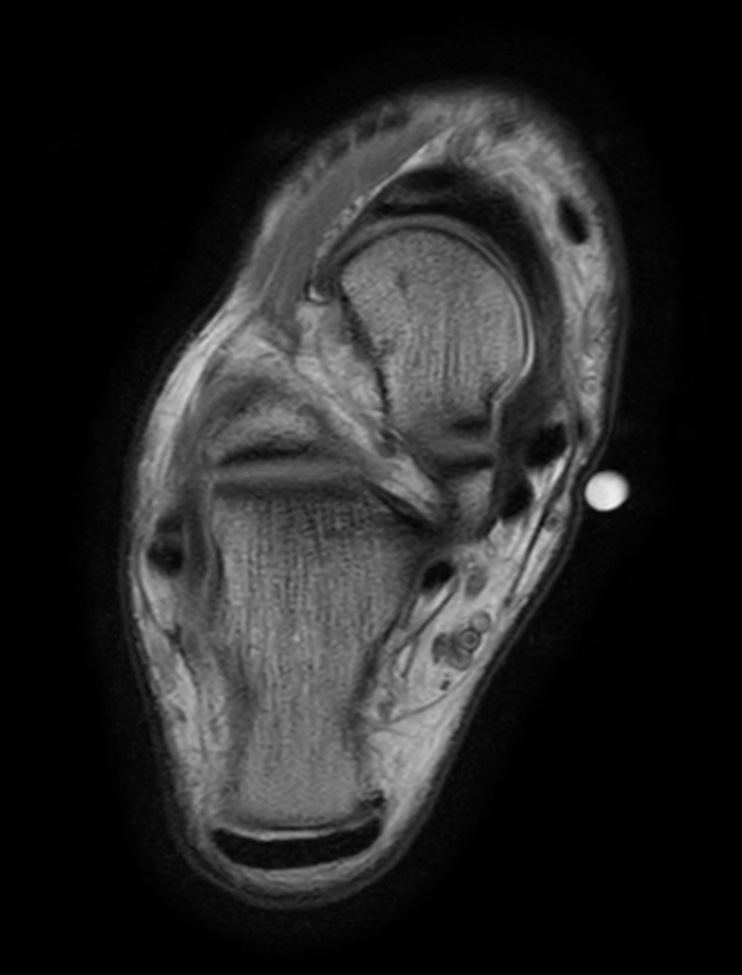

Axial PDw TSE - mDIXON XD (In Phase)

Axial PDw TSE - mDIXON XD (Water only)